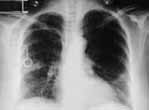

No se pudo efectuar estudio con galio como marcador de la actividad tumoral previo al tratamiento, por severa dificultad respiratoria; se realizó quimioterapia 6 ciclos de tipo CHOP (ciclofosfamida, adriamicina, vincristina y prednisona) con marcada mejoría clínica. La radiografía de tórax 3 meses después del tratamiento demuestra mejoría casi completa de los infiltrados (Fig. 3), y una broncoscopia de control mostró la presencia de puentes mucosos sin presencia de tumor en la biopsia.

Figura No.3 Mejoría radiológica posterior a la quimioterapia.